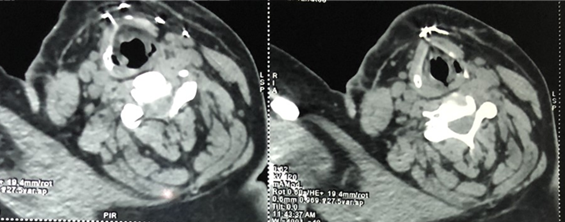

A cervico-thoracic CT-scan was done objectifying, in addition to multiple

subcutaneous metallic foreign bodies (Figure

2), a metallic wire which has migrated in the supra clavicular area and

Figure

2: Cervical CT-scan

- cross section showing subcutaneous steel wires in front of the thyroid

cartilage